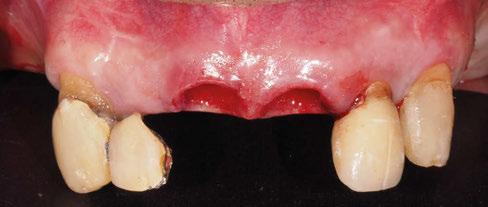

A partir del estudio radiológico y de las imágenes fotográficas podemos observar edentulismo de 17, 15, 14, 12,

25, 26, 28, 37, 38, 47 y 48. Presentaba corona desajustada en 13 con extensión en 12, implantes en 35-36, 45-46, con coronas ferulizadas en 35-36, 45-46, y dientes anteriores superiores con enfermedad periodontal Grado IV.

2. Exploración de tejidos blandos

El paciente presentaba biotipo periodontal grueso, con márgenes asimétricos, con recesiones gingivales a nivel de 11 y 13 y pérdida de tejidos blandos interproximales.

3. Exploración de tejidos duros

En la exploración radiográfica (OPG, CBCT) observamos la existencia de pérdida ósea interproximal, lesión apical a nivel de la raíz mesial del 27 y el cordal del primer cuadrante incluido y neumatización sinusal del primer y segundo cuadrante.

En el CBCT observamos pérdida ósea posterior superior debida a la neumatización de los senos maxilares izquierdo y derecho. También podemos observar disponibilidad ósea apical suficiente en dientes antero-superiores para la realización de una Implantología inmediata y corticales vestibulares y palatinas conservadas.